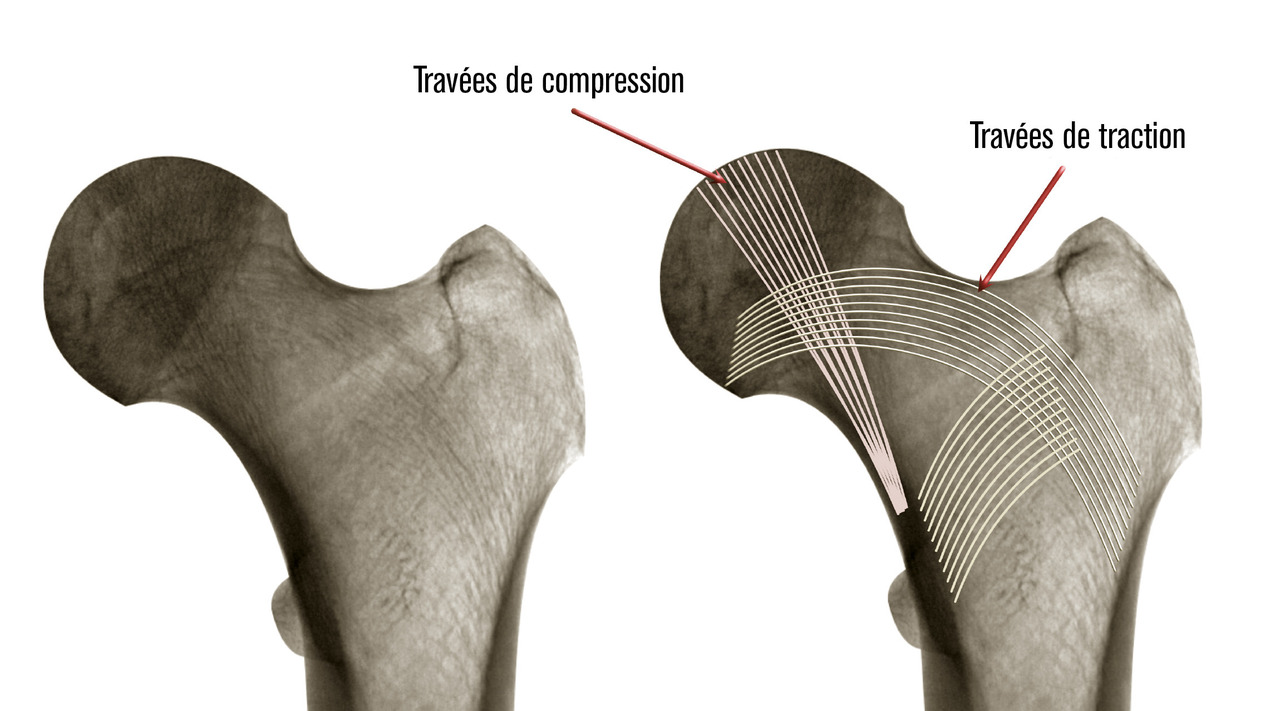

L’extrémité supérieure du fémur se compose de trois régions bien distinctes (fig. 1) : la tête fémorale représentant à peu près deux tiers de sphère est recouverte de cartilage ; le col fémoral assurant la jonction entre la tête et le massif trochantérien ; le massif trochantérien entre la ligne intertrochantérienne et la zone située jusqu’à 2,5 cm sous le petit trochanter. La tête et le col fémoral sont intracapsulaires. Le col est composé d’un os cortical. Il est soumis à des contraintes en cisaillement auxquelles un système de travées osseuses ogival lui permet de résister (fig. 2). Le massif trochantérien est formé d’un os beaucoup plus spongieux et bien vascularisé. La tête fémorale est essentiellement vascularisée par l’artère circonflexe médiale (fig. 3) qui aborde le col fémoral le long de la ligne intertrochantérienne, court le long du col à sa partie supérieure et donne ses branches terminales à la tête fémorale. Ainsi, toute fracture déplacée du col risque de léser la vascularisation céphalique et d’entraîner une ostéonécrose. En effet, la vascularisation assurée par l’artère du ligament rond et les quelques vaisseaux venant de l'artère circonflexe latérale ne suffisent pas à suppléer cette absence de vascularisation. Ce système vasculaire n’est pas altéré dans les fractures du massif trochantérien.